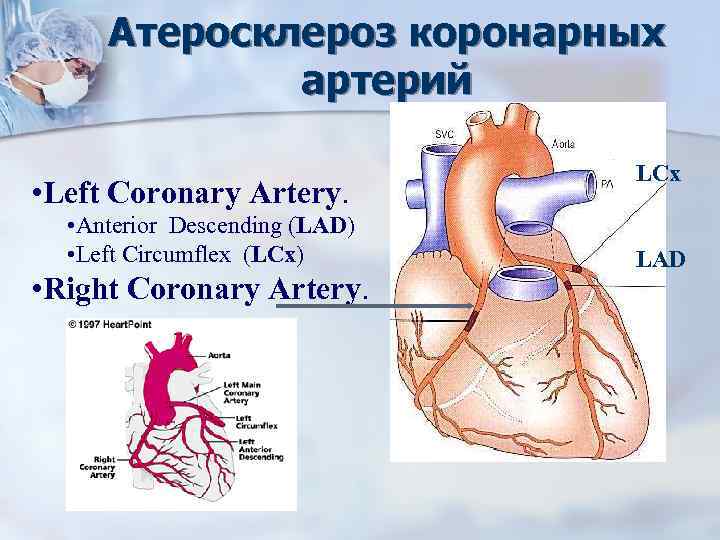

Нормальный диаметр корня аорты: медицинские нормы и отклонения